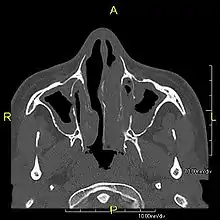

Around 80% of people with primary ciliary dyskinesia experience respiratory problems beginning within a day of birth. Many have a collapsed lobe of the lung and blood oxygen low enough to require treatment with supplemental oxygen.[1] Within the first few months of life, most develop a chronic mucus-producing cough and runny nose.[1] The main consequence of impaired ciliary function is reduced or absent mucus clearance from the lungs, and susceptibility to chronic recurrent respiratory infections, including sinusitis, bronchitis, pneumonia, and otitis media. Progressive damage to the respiratory system is common, including progressive bronchiectasis beginning in early childhood, and sinus disease (sometimes becoming severe in adults). However, diagnosis is often missed early in life despite the characteristic signs and symptoms.[2] In males, immotility of sperm can lead to infertility, although conception remains possible through the use of in vitro fertilization, there also are reported cases where sperm were able to move.[8] Trials have also shown that there is a marked reduction in fertility in females with Kartagener's syndrome due to dysfunction of the oviductal cilia.[9]

Many affected individuals experience hearing loss and show symptoms of otitis media which demonstrates variable responsiveness to the insertion of myringotomy tubes or grommets. Some patients have a poor sense of smell, which is believed to accompany high mucus production in the sinuses (although others report normal – or even acute – sensitivity to smell and taste). Clinical progression of the disease is variable, with lung transplantation required in severe cases. Susceptibility to infections can be drastically reduced by an early diagnosis. Treatment with various chest physiotherapy techniques has been observed to reduce the incidence of lung infection and to slow the progression of bronchiectasis dramatically. Aggressive treatment of sinus disease beginning at an early age is believed to slow long-term sinus damage (although this has not yet been adequately documented). Aggressive measures to enhance clearance of mucus, prevent respiratory infections, and treat bacterial superinfections have been observed to slow lung-disease progression. The predicted incidence is 1 in approximately 7500.[10]

Several diagnostic tests for this condition have been proposed.[5] These include nasal nitric oxide levels as a screening test, light microscopy of biopsies for ciliary beat pattern and frequency and electron microscopic examination of dynein arms, as the definite diagnosis method. Genetic testing has also been proposed but this is difficult given that there are multiple genes involved.[6]